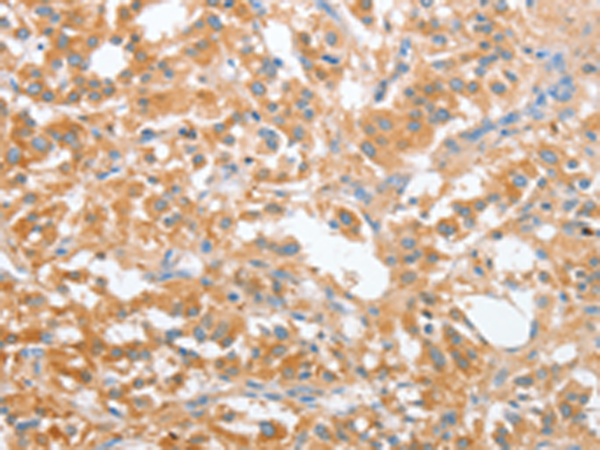

分类: 科研抗体货号: P08110别名:应用: IHC反应种属: Human